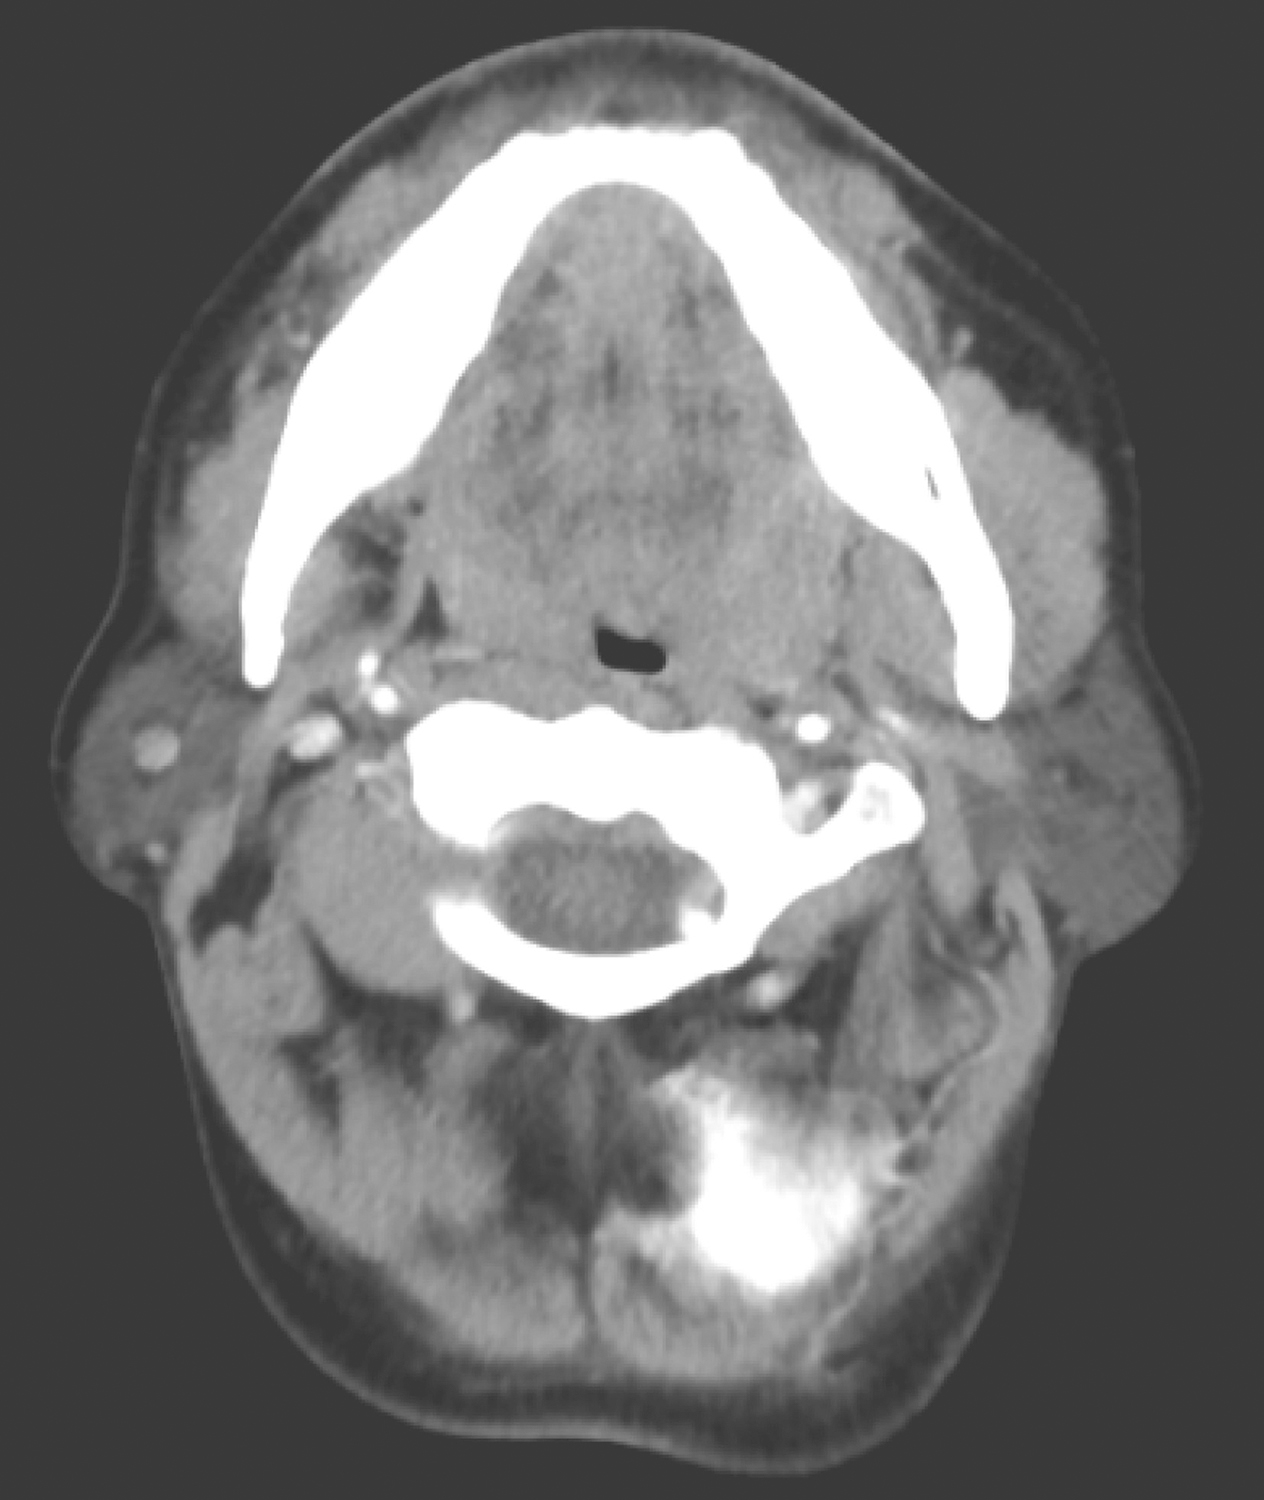

1.2016年9月30日颈胸部CT

双侧扁桃体饱满,边界欠清楚(图1)。双侧颈静脉链周围、颌下、颏下多发肿大淋巴结,大者短径约1.0cm,余颈部、纵隔及肺门未见明显肿大淋巴结。鼻咽、下咽、喉及甲状腺未见明确异常。双肺未见明确结节及实变影。未见胸腔积液及心包积液。

影像学诊断:

扁桃体饱满,请结合MR。颈部淋巴结转移,侵犯左侧咽旁间隙,请结合临床。

图1颈胸部CT示双侧扁桃体饱满,边界欠清楚